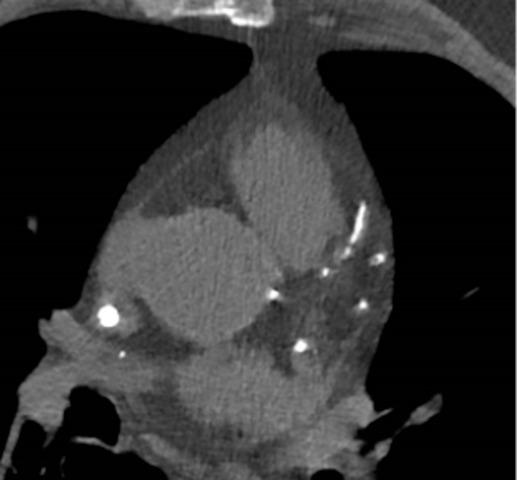

Chronic kidney disease (CKD) is affecting more and more individuals over time. The importance of the increased prevalence is enhanced by the close association with the increased risk of poor individual outcomes such as death, fatal and non-fatal cardiovascular (CV) events and progression to end stage kidney disease (ESKD). ESKD requires replacement treatment such as hemodialysis (HD), a particular and complex context that unfortunately has been rarely considered in observational studies in the last few decades. The current perspective of HD as a bridge to kidney transplant requires greater attention from observational and experimental research both in the prevention and treatment of CV events in ESKD patients. We present a narrative review by performing a literature review to extrapolate the most significant articles exploring the CV risk, in particular coronary artery disease (CAD), in ESKD and evaluating possible innovative diagnostic and therapeutic tools in these patients. The risk of CAD increases linearly when the estimated glomerular filtration rate (eGFR) declines and reached the most significant level in ESKD patients. Several diagnostic techniques have been evaluated to predict CAD in ESKD such as laboratory tests (Troponin-T, N-terminal pro b-type natriuretic peptide, alkaline phosphatase), echocardiography and imaging techniques for vascular calcifications evaluation. Similarly, treatment is based on lifestyle changes, medical therapy and invasive techniques such as coronary artery bypass grafting (CABG) and percutaneous coronary intervention (PCI). Unfortunately in the literature there are no clear indications of the usefulness and validity of biomarkers and possible treatments in ESKD patients. Considering the ESKD weight in terms of prevalence and costs it is necessary to implement clinical research in order to develop prognostic reliable biomarkers for CV and CAD risk prediction, in patients with ESKD. It should be highlighted that HD is a peculiar setting that offers the opportunity to implement research and facilitates patient monitoring by favoring the design of clinical trials.

随着时间的推移,慢性肾脏病(CKD)影响着越来越多的人。其患病率上升的重要性因与不良个体结局风险增加密切相关而得到强化,这些不良结局包括死亡、致命和非致命性心血管(CV)事件以及进展至终末期肾病(ESKD)。ESKD需要诸如血液透析(HD)之类的替代治疗,这是一种特殊且复杂的情况,遗憾的是在过去几十年的观察性研究中很少被考虑。当前将HD视为肾移植桥梁的观点需要观察性和实验性研究给予更多关注,以预防和治疗ESKD患者的CV事件。我们通过进行文献综述来呈现一篇叙述性综述,以推断探索ESKD患者CV风险,特别是冠状动脉疾病(CAD)的最重要文章,并评估这些患者可能的创新诊断和治疗工具。当估计肾小球滤过率(eGFR)下降时,CAD风险呈线性增加,并在ESKD患者中达到最高水平。已经评估了几种诊断技术来预测ESKD患者的CAD,如实验室检查(肌钙蛋白-T、N末端B型利钠肽原、碱性磷酸酶)、超声心动图以及用于评估血管钙化的成像技术。同样,治疗基于生活方式改变、药物治疗以及诸如冠状动脉旁路移植术(CABG)和经皮冠状动脉介入治疗(PCI)等侵入性技术。遗憾的是,文献中对于ESKD患者生物标志物和可能治疗方法的有用性和有效性没有明确的指示。考虑到ESKD在患病率和成本方面的权重,有必要开展临床研究,以便为ESKD患者开发用于CV和CAD风险预测的可靠预后生物标志物。应当强调的是,HD是一种特殊的环境,它提供了开展研究的机会,并通过有利于临床试验的设计来促进患者监测。